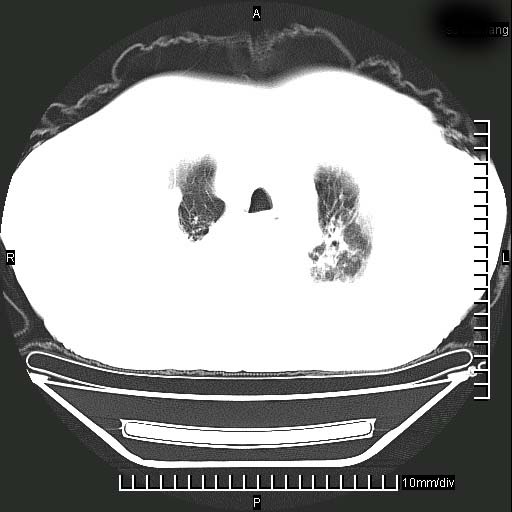

1)两肺继发性肺结核。2)右侧胸膜增厚+少量胸腔积液。